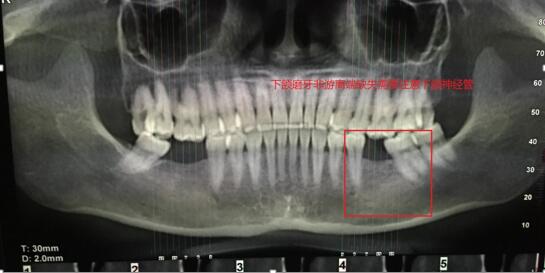

吳X,女,46歲;主訴: 左下后牙缺失3月余,影響美觀?,F(xiàn)病史:左下后牙3個(gè)月前因牙體治療失敗在我院頜面外科拔除,現(xiàn)要求種植修復(fù)。既往史:否認(rèn)系統(tǒng)病史。檢查:36缺失,拔牙創(chuàng)愈合良好,缺失間隙近遠(yuǎn)中寬度7mm,頜齦距離正常,頰舌向?qū)挾燃s8mm。輔查:口腔CBCT顯示36可用牙槽骨高度(牙槽嵴頂?shù)较骂M神經(jīng)管)約18-19mm,頰舌側(cè)寬度12mm,骨質(zhì)正常,無(wú)疏松影像,鄰牙根尖周無(wú)暗影。 診斷: 36牙列缺損。治療計(jì)劃:種植義齒修復(fù)36牙列缺損。 處理: 1. 與患者說(shuō)明種植牙修復(fù)的治療過(guò)程,注意事項(xiàng)和費(fèi)用,患者同意種植修復(fù)。 2. 血常規(guī)檢查,全口牙潔治。 3. 患者口內(nèi)藻酸鹽...